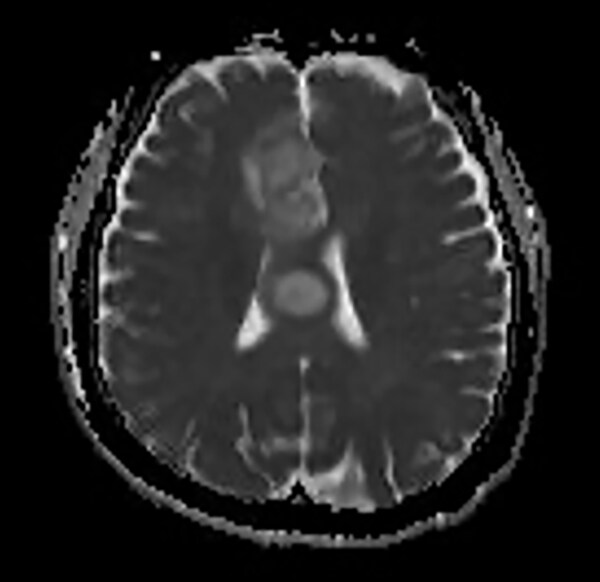

T1WI低信号、T2WI高信号、FLAIR高信号、DWIでやや高信号の腫瘤。Gdで腫瘤は造影されず、DSC-Perfusionでは辺縁~中心部に一部血流の高い部分あり。MRスペクトロスコピーではCho上昇とNAA低下がみられる。Low grade gliomaを疑う。後日、摘出手術が施行され、病理診断はoligodendroglioma NOS(Grade 2)であった。